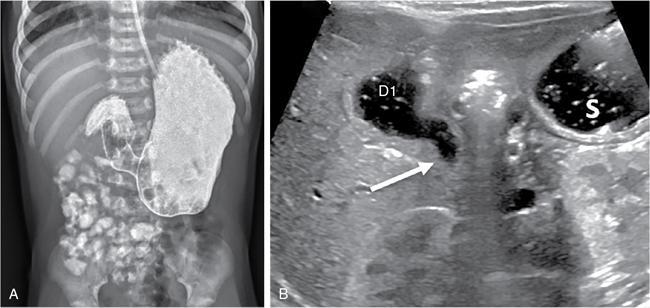

C.V. Kanimozhi, S. Muralinath, Raveendran J. Many of the important congenital gastrointestinal abnormalities present acutely in the newborn; some present much later. These include obstructive gastrointestinal lesions that present with vomiting, abdominal distension and not having passed meconium. The imaging modalities that are most commonly used in the evaluation of neonatal gastrointestinal abnormalities are plain films, contrast studies and ultrasound. Plain films remain a valuable tool in the assessment of abdominal abnormalities in the neonate. They are also an excellent guide to determining the next proper imaging study to perform for a particular problem. Certain neonatal bowel disorders have a pathognomonic appearance on radiographs obviating the need for further imaging. The essential and basic view to be done at the bedside is the supine view of the abdomen. In the evaluation of abnormal intra-abdominal gas patterns, alternative decubitus views, prone and supine cross-table lateral views may be taken. Erect view is not utilized in neonatal practice at the bedside as it is impossible to restrain a neonate in that position and unnecessarily subjects the neonate to stress, which may worsen the condition of an already sick baby. Evaluation of the bowel gas pattern and the anatomic localization of the intra-abdominal gas is the key to diagnosis in the evaluation of diseases of the GI tract. The bowel gas in the neonate is essentially swallowed air (Box 7.8.1). Movement of Air Through the GIT in a Term Neonate Most infants pass meconium by 24 hours of life. In order to interpret the bowel gas pattern and determine if an abnormality is present, it is crucial to know the age of the neonate (hours since birth) at the time the radiograph was taken. When there is impaired swallowing, such as due to CNS depression or in prematurity, radiographs show diminished bowel gas. In cases of bowel atresia, radiographs show absence of bowel gas in distal segments. Thus, the distribution of bowel gas and its pattern serve as pointers to the diagnosis. After the radiograph has been done, depending on the findings, an ultrasound or fluoroscopic contrast study may be performed next. The radiologist should tailor the contrast study to suit the particular patient and the clinical question that needs to be answered. In cases of suspected high GI obstruction, an upper GI contrast series is study of choice; in cases of suspected low GI obstruction a contrast enema should be performed to delineate the anatomy. When performing fluoroscopic studies, it is important to bear in mind the radiation dose and to adopt the ALARA principle. Minimizing radiation exposure in children is important because they are more sensitive to the effects of radiation and have a longer life expectancy than adults. The technical parameters must be adapted to paediatric imaging. Ultrasound is a useful bedside tool particularly in the sick neonate. In neonates, the sonographic image resolution is excellent due to the lack of significant body fat. In neonates, exquisite images of the abdomen can be obtained with the high-resolution ultrasound probe, which permits imaging the bowel wall in great detail. In addition, it can also reveal other causes for abdominal distension or vomiting. In this chapter, we will discuss the aetiology, clinical presentation and imaging appearances of congenital neonatal gastrointestinal abnormalities. We will also discuss common acquired abnormalities that present in the neonatal period, namely necrotizing enterocolitis. Congenital oesophageal malformations of the newborn include the various types of atresia (with and without fistula) and oesophageal duplications. Oesophageal atresia with or without tracheoesophageal fistula (TEF) is a common congenital anomaly that manifests in the neonatal period. It is also the most important congenital malformation of the oesophagus. Oesophageal atresia is commonly associated with other anomalies of the gastrointestinal tract such as imperforate anus, pyloric atresia, duodenal atresia and annular pancreas and less frequently with anomalies of the cardiac and genitourinary systems. About 20% of patients with oesophageal atresia have the VACTERL syndrome (vertebral anomaly, anorectal atresia, cardiac lesion, tracheoesophageal fistula, renal anomaly, limb defect). Oesophageal stenosis and webs may be associated with oesophageal atresia. The aetiology of oesophageal atresia and TEF is not completely understood. Faulty separation of the primitive trachea and oesophagus is the most widely accepted theory. The way the primitive foregut cleaves into a ventral (tracheal) passage and a dorsal (oesophageal) passage is a complex process and is poorly understood. Folds developing from the longitudinal ridge is said to separate the two. When the separation has an extreme tracheal bias, an oesophageal atresia occurs and if the bias is towards the oesophagus, then a tracheal atresia ensues. Incomplete separation may result in fistula of various types. Oesophageal atresia and TEF are classified depending upon the absence or presence and location of the fistula between the oesophagus and the trachea (Fig. 7.8.1). Neonates present within a few hours of birth with excessive salivation, drooling, cyanotic spells and regurgitation of feeds. The inability to successfully pass a nasogastric tube strongly suggests oesophageal atresia. Newborns with H-type fistula may have feeding difficulties and choking, but often the presentation and diagnosis is only later in infancy when the patient presents with cough, choking episodes and recurrent pneumonia. The role of imaging is to diagnose, define the anatomy to the best extent possible and evaluate for other anomalies to provide a clear picture for the paediatric surgeon. For example, it is important for the surgeon to know the side of the aortic arch in order to lateralize the surgical approach. Chest X-ray and Echo can localize the arch and determine if an anomalous right-sided aortic arch is present. Plain films of the chest including abdomen need to be obtained. The radiograph will demonstrate the air-filled distended proximal oesophageal pouch. If a nasogastric tube has been inserted, the coiled tube will be seen within the pouch. Absence of bowel gas in the abdomen indicates oesophageal atresia without a distal fistula – types A and B have this radiographic appearance (Fig. 7.8.2). The presence of gas in the gastrointestinal tract indicates the presence of a distal fistula – types C and D (Fig. 7.8.3). Contrast studies to delineate the proximal pouch are generally not indicated. Coiling of the nasogastric tube in the proximal pouch confirms the diagnosis. Chest radiographs frequently show changes of consolidation due to aspiration pneumonia, most often involving the right upper lobe (Fig. 7.8.4). In cases of H-type fistula, plain films are nonspecific and the diagnosis depends on contrast studies. Radiological diagnosis is made by means of a tube oesophagogram. This study has the potential risk of aspiration and the neonate may desaturate quite rapidly. Hence, it is important to have neonatal emergency resuscitation at hand. The tube oesophagogram is performed under fluoroscopy with the baby in lateral- or steep-prone oblique position. The NG tube is placed at the oesophagogastric junction and is gradually withdrawn while simultaneously injecting contrast. Nonionic low-osmolar contrast agent should be used. Most of the H-type fistulas are located in the lower cervical and upper thoracic regions with the fistula typically coursing upward and forward from the oesophagus. In the presence of a fistula, the contrast will be seen passing into the trachea in an upwardly oblique configuration. Aspiration during the study can also cause the contrast to appear in the tracheal tree and the lungs. It needs to be established whether the contrast has passed through the fistula or whether aspiration has occurred. Recording of the fluoroscopic run and reviewing the images may be required to make this distinction. Repeat examination may be required. Demonstration of H-type fistula can be difficult radiologically. In such patients, bronchoscopy with transfistula guidewire placement has been found to be of use. MRI – High resolution structural MRI is a new technique that is being used to visualize tracheobronchial anatomy. The disadvantage with radiographs is that one cannot determine the anatomic subtype of TEF, the site of the TEF or the length of the gap between the atretic segments. Using ultrashort echotime (UTE) MR imaging, it is possible to visualize the exact site of the fistula and assess the size of the oesophageal gap. This can aid presurgical planning and help identify infants at risk for complications, such as those with a long oesophageal gap. Imaging plays an important role in the evaluation of early and late complications of atresia repair. Early complications include anastomotic leaks and are seen in about 10%–20% of cases. Oesophageal contrast study, using a nonionic low-osmolar contrast agent, is performed to demonstrate the leak at the anastomotic site (Fig. 7.8.5). Leaks are associated with a greater incidence of subsequent stricture development. Anastomotic stricture is a common complication seen in about 30%–40% of cases. Often there is a slight narrowing at the site of repair without the patient having any difficulty in swallowing (Fig. 7.8.6). The anastomotic narrowing is clinically relevant only if the patient has dysphagia; such cases respond to dilatations. Recurrent TEF occurs in 5%–10% of cases after oesophageal atresia repair. Late complications include dysphagia, gastroesophageal reflux, tracheomalacia and chest wall deformities. Dysphagia can occur post-operatively due to abnormal oesophageal motility. Oesophageal dysmotility can be caused by abnormal neural development of the oesophagus or may result from complication of atresia repair. Gastroesophageal reflux affects 40%–65% of patients following oesophageal repair. It may be due to an intrinsic deficiency in the motor function of the oesophagus; this may get exacerbated postrepair due to an alteration of the anatomical gastroesophageal junction. Oesophageal atresia key imaging finding – X-ray shows NG tube coiled in proximal oesophageal pouch. The stomach is divided into the fundus and body proximally and the antrum distally. The antrum is divided by the sulcus intermedius into a proximal pyloric vestibule and a distal pyloric antrum or pyloric canal. This canal terminates into the pyloric sphincter beyond which is the duodenum. Congenital anomalies of the stomach that manifest in the neonatal period are uncommon. Hypertrophic pyloric stenosis (HPS) is the most common surgical cause of vomiting in infants. The incidence is 2–5 per 1000 live births, with geographic and racial variations. Compared to Caucasians, HPS is less common amongst Asian populations. The male to female ratio is approximately 4:1, occurring more commonly in the first-born child. The precise aetiology is unknown. Overactivity or prolonged spasm of the circular muscle of the pyloric antrum is thought to be the primary problem in these infants. This spasm leads to muscle hypertrophy and obstruction. Multiple hypotheses have been proposed for this prolonged spasm. One is that some infants are genetically predisposed to increased gastrin production which leads to a vicious cycle of hyperacidity, increased gastric contraction and secondary development of muscular hypertrophy. Most infants present after the first week of life and before 3–4 months of age. Typical symptoms include projectile nonbilious vomiting, regurgitation and difficulty in feeding. The gastric outlet obstruction can lead to emaciation. The distended stomach with active peristaltic activity may be visible through the thin abdominal wall. In the past barium upper GI series was the mainstay diagnostic tool for HPS. Prior to the barium study, the stomach may need to be decompressed via a nasogastric tube. The classic sign on a barium study is the ‘string sign’ (Fig. 7.8.7) produced by a thin stream of barium in an elongated narrowed pyloric canal; the canal typically curves upward. In severe cases, complete obstruction will lead to the ‘beak sign’, which is produced by beaking of the contrast as it enters the pyloric canal. With lesser degrees of obstruction, the ‘double track sign’ is seen. This is produced when the pyloric canal is flattened and the barium accumulates in the crevices along either side of the flattened canal. Pylorospasm can transiently mimic the findings of HPS. Currently, ultrasound is the modality of choice for the diagnosis of HPS and upper GI studies are seldom used. Ultrasound is considered the ‘gold standard’ as it allows direct examination of the pyloric muscle and also provides the ability to perform a dynamic study. The ultrasound examination is performed with a linear high-frequency transducer (6–10 MHz). The examination begins with the baby in supine position. First, the antropyloric region is identified; the pylorus is usually located medial and posterior to the gall bladder. The normal pyloric muscle is a thin hypoechoic layer that measures 2 mm or less. The abnormal pyloric canal shows thickening of the muscle and the mucosa to varying degrees. In cross section, it is seen as a hypoechoic structure likened to a doughnut. The length of the canal is measured in long section where its appearance is likened to the cervix. The sonographic diagnostic criteria for HPS are a thickened muscle layer measuring ≥3 mm and an elongated pyloric channel ≥15 mm (Fig. 7.8.8). The diameter of the pylorus in cross section was also one of the originally used measurements. However, due to a significant overlap between normal and abnormal, this measurement is no longer utilized. Additional ultrasound findings of HPS are hypertrophy of the pyloric mucosa and a distended, actively peristalsing stomach. The hypertrophied redundant mucosa projects into the antrum analogous to the ‘nipple sign’ in barium studies (Fig. 7.8.8D.). Colour Doppler imaging shows increased flow in the muscle and mucosa. The above-described measurements of pyloric muscle thickness and canal length are vital to diagnosis. However, dynamic assessment is equally important. One must evaluate the antropyloric region over a period of time to ensure persistent stenosis without evidence of relaxation and opening of the canal. A distensible antropyloric region with normal passage of gastric contents excludes HPS. Transient contractions of the pylorus or pylorospasm can mimic pyloric stenosis in both measurement and appearance. With observation over a period of time, opening of the pyloric canal may be visualized. Hence the key to diagnosis of HPS is persistent non-relaxing thickened musculature. Gas in the stomach may obscure the pylorus. To avoid this, place the infant in an oblique position, right side down which will allow the antrum to fill with fluid. Conversely, an overdistended fluid-filled stomach can displace the pylorus dorsally. In such cases, turning the infant left side down will displace the fluid towards the fundus and will allow the pylorus to rise to a more anterior position. At times, equivocal examinations may occur where the muscle measures 2–3 mm in thickness and does not relax. In these patients, careful monitoring with repeat ultrasound is warranted. In a few cases, the abnormalities advance overtime to fully developed HPS. Hence in such equivocal cases if vomiting continues, follow-up ultrasound is advisable. Surgical pyloromyotomy is the treatment for HPS. On ultrasound, the myotomy site can be seen as an interruption in the hypoechoic doughnut. It is important to be aware that postsurgery, the pyloric muscle may remain thickened for up to 5 months with a gradual return to normal thickness. In the first week after surgery, the muscle can be the same thickness as pre-op or even thicker. One should not be alarmed by this appearance. The dimensions gradually return to normal over the course of a few months. Postop if the child is thriving well, there is no need for imaging to be performed. HPS key imaging finding: On high-frequency ultrasound muscle thickness ≥3 mm and elongated pyloric channel ≥15 mm. Pyloric atresia is a rare anomaly comprising less than 1% of all intestinal atresias. Pyloric atresia is classified into three types (Fig. 7.8.9): The exact aetiology remains controversial. In the past, it was postulated that failure of recanalization of the gastrointestinal tract was the cause. Recent evidence suggests that pyloric atresia is the result of localized vascular occlusion. This vascular theory suggests that the atresia is due to focal ischemia secondary to intrauterine stress, vascular insult or anoxia. In complete obstruction, the presentation is in the neonatal period with nonbilious vomiting within the first few hours of life. Incomplete obstruction due to a diaphragm has a variable presentation depending on the size of the orifice. These patients can present later in life with intermittent vomiting or postprandial vomiting. In complete pyloric atresia, a dilated stomach is present on radiographs with absence of gas in the distal bowel. This is known as ‘single bubble’ appearance (Fig. 7.8.10). This appearance is diagnostic and in such cases, contrast studies are generally not required. In the membranous type, there is an opening in the centre of the diaphragm and hence, the obstruction is usually incomplete. On radiographs, the stomach is distended and lesser than normal volumes of air is present in the small bowel (Fig. 7.8.11). On upper GI barium studies, a diaphragm is seen as a thin (2–4 mm) linear filling defect that spans across the antrum with a normal pyloric canal. One needs to determine on fluoroscopy whether the membrane is causing significant obstruction or not. If obstructing, the diaphragm will balloon out with gastric peristalsis. In incompletely obstructing diaphragms, the edges of the diaphragm will be visible but there will no obstruction or ballooning. Pyloric atresia key imaging finding: X-ray abdomen – ‘single bubble’ appearance. Microgastria is an extremely rare congenital abnormality wherein the stomach is small, midline in position and typically associated with a dilated oesophagus. The stomach is represented by a small tubular structure without recognizable differentiation into fundus, body, antrum and pylorus. Agastria is the most extreme form of microgastria. Microgastria is frequently associated with other anomalies such as polysplenia-asplenia syndrome, malrotation, gastrointestinal atresia and vertebral, cardiac, renal and limb reduction anomalies (VACTREL association). Microgastria occurs due to arrest in early development of the foregut. In the 5th week of gestation, dilatation of the region of the future stomach occurs. Ninety-degree rotation of the stomach occurs in the 6th week, followed by development of the greater and lesser curves and growth of the fundus in the subsequent weeks. Arrest of this process leads to microgastria, with severity dependent on the stage at which arrest occurs. The development of spleen within the dorsal mesogastrium of stomach explains the association of microgastria and splenic anomalies. The association of limb, cardiac, tracheoesophageal, vertebral and renal anomalies has been attributed to impairment of early mesodermal development. The symptoms are related to the effects of the inadequate stomach and dilated oesophagus or due to the associated severe anomalies. These babies may present with feeding difficulties, failure to thrive, vomiting, recurrent aspiration and malnutrition due to severe gastroesophageal reflux. Radiographs may show an absent stomach bubble; in some cases, the shadow of the dilated oesophagus may be seen in the lower chest. On an upper GI study, the stomach appears small, tubular and midline in position. There is often associated severe gastroesophageal reflux and a very dilated oesophagus. The oesophagus dilates to take over the storage function of the inadequate stomach. Additional imaging studies are required to identify the associated anomalies. Key imaging finding: Upper GI study – Small, tubular stomach located in the midline. Congenital anomalies of the duodenum present with obstructive symptoms. The primary considerations for bilious vomiting in the neonate are duodenal atresia, duodenal stenosis, annular pancreas and malrotation with midgut volvulus. The most important investigation in the majority of these patients is an upper GI series as it accurately demonstrates the level and nature of duodenal obstruction. Duodenal atresia may be seen in isolation or in the setting of trisomy 21 (about 30% of patients have Down’s syndrome). Associated anomalies are frequent and include malrotation, oesophageal atresia, annular pancreas, biliary atresia, congenital heart disease and vertebral anomalies. Duodenal atresia is due to failure of gut recanalization during embryologic development leading to complete obstruction. Normal recanalization of the duodenum occurs between the 9th and 12th weeks of gestation. Failure of this process results in duodenal atresia. In most cases (roughly 80%), the atresia is distal to the ampulla of Vater. Neonates with duodenal atresia present with bilious vomiting in the first few hours of life. In those patients where the atresia is proximal to the ampulla, the vomitus will be nonbilious. In duodenal atresia, air is present in the stomach and duodenum with no gas in the distal intestinal tract. Dilatation of the stomach and the duodenum produces the characteristic ‘double bubble’ appearance on radiographs (Fig. 7.8.12). This appearance is diagnostic and rarely requires further imaging. Key imaging finding: X-ray abdomen – ‘double bubble’ appearance Duodenal stenosis and duodenal web cause partial obstruction due to a narrowed segment or thin membrane, respectively. As with duodenal atresia, both these conditions show a strong association with malrotation, annular pancreas and a preduodenal portal vein. Duodenal web and stenosis is due to incomplete recanalization of typically the second part of the duodenum. In babies with duodenal stenosis, the presentation and clinical findings depend on the degree of stenosis. Those with less severe forms of stenosis may present later in life. Radiographs in duodenal stenosis and web show a distended stomach and duodenum. Since the obstruction is incomplete, gas will be present in the distal loops. On upper GI study, duodenal stenosis is seen as a focal narrowing in the second part of the duodenum (Fig. 7.8.13). In duodenal web, a thin membrane/diaphragm is seen that partially obstructs the lumen, usually in the second segment of duodenum. The membrane is often difficult to demonstrate (Fig. 7.8.14). A ‘windsock deformity’ may also be seen; this appears as a proximal dilated duodenal segment with contrast outlining a thin web that bulges into a distal nondilated segment. This windsock duodenum is seldom seen in the neonatal period as this appearance is due to stretching of the membrane over time. Key imaging finding: Upper GI study – narrowing in second part of duodenum. Annular pancreas is an anomalous band of pancreatic tissue that encircles the second portion of duodenum. Annular pancreas may result in extrinsic duodenal obstruction. Often there is associated intrinsic duodenal abnormality viz. some degree of duodenal atresia, web or stenosis. As in duodenal atresia, associated anomalies such as trisomy 21, cardiac defects, malrotation, oesophageal atresia and anal atresia can occur. The pancreas arises as two endodermal outgrowths, ventral and dorsal buds, from the duodenum. The head of the pancreas derives from the smaller ventral bud. Annular pancreas occurs if the ventral bud becomes tethered to the duodenum or it fails to rotate completely before fusion with the dorsal bud. The clinical presentation is similar to duodenal atresia or stenosis. If the obstruction is complete, presentation is in the neonatal period with bilious vomiting. Cases of incomplete obstruction may remain asymptomatic until adulthood. Annular pancreas is the second most common condition to produce a ‘double bubble’ appearance on radiographs. Plain films will show dilatation of the stomach and duodenum. Upper GI contrast study will show narrowing of the second part of duodenum (Fig. 7.8.15). On ultrasound pancreatic tissue may be seen encircling the second part of duodenum (Fig. 7.8.16). At times the appearance may resemble a mass at the level of head of pancreas.